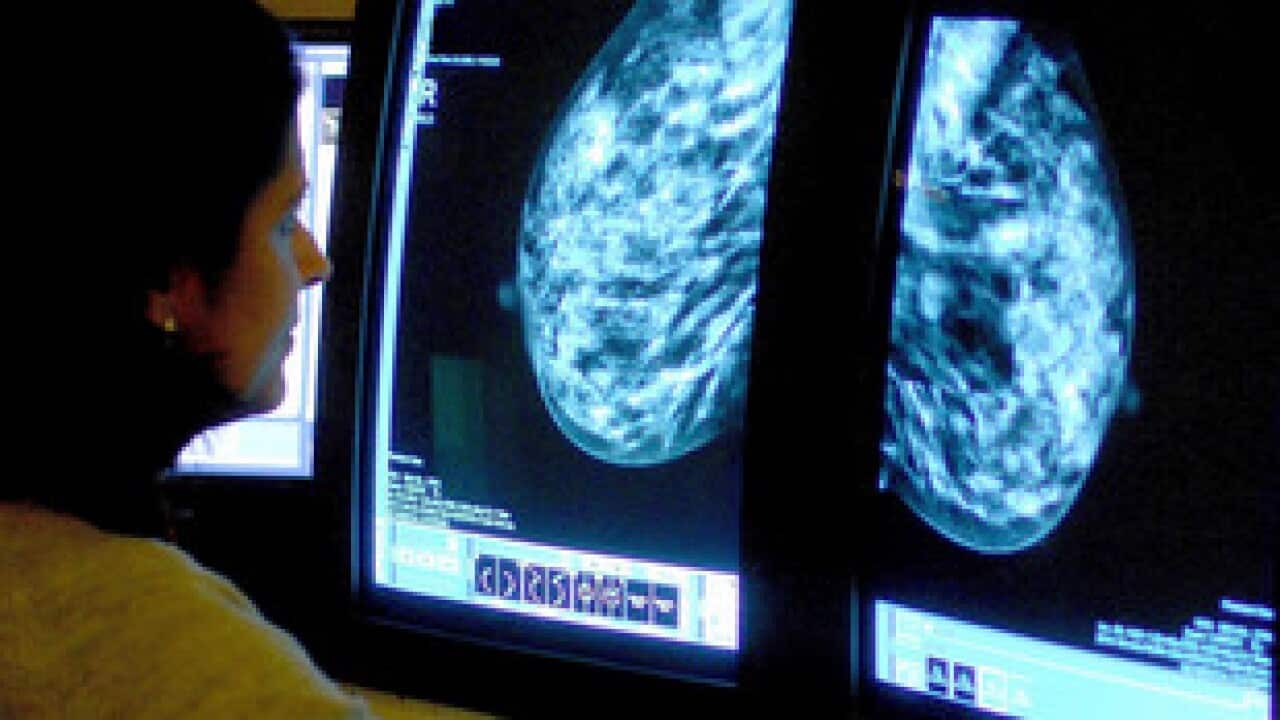

維州乳腺檢查中心的中文工作員工 Gracy Wu (吳楊) 表示,這些都是坊間的一些誤解,例如初期的乳腺癌細胞可能比一粒米還要小,靠自己觸摸來分辨癌細胞並不可靠。

X 光檢查的操作人員均是女性,檢查需時一般在 10 分鐘左右,至於有關乳腺檢查的詳情,請瀏覽 Breastscreen Victoria 的網站。